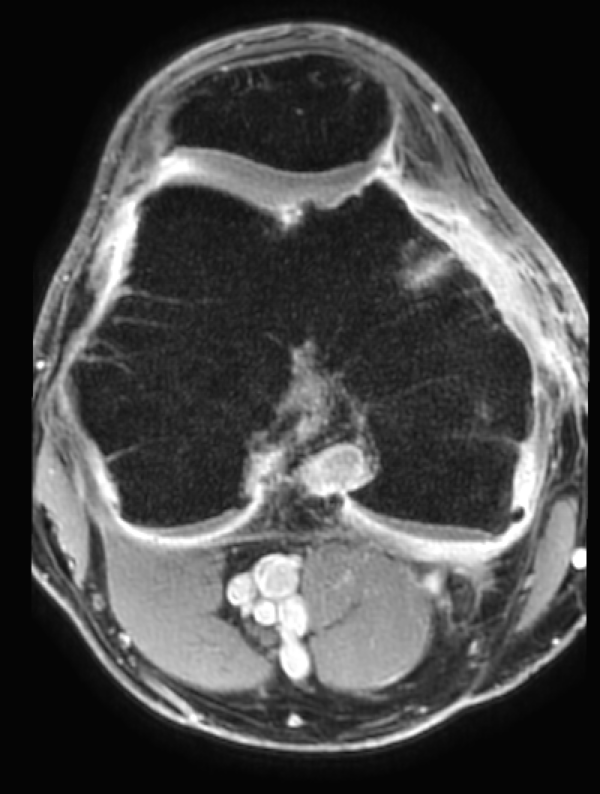

• IRM : Cet examen permet d'évaluer l'état des structures osseuses et articulaires du genou, et de détecter des signes d'arthrose ou d'inflammation. Plus précise que les radiographies, elle peut détecter des signes de synovite lorsqu'elle est réalisée après injection.

IRM du genou avec injection